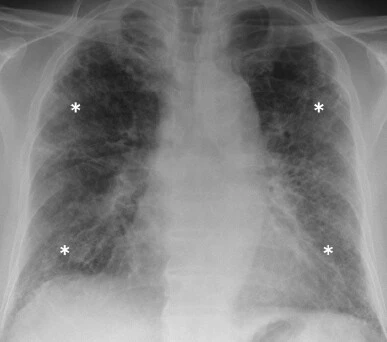

此外,胸片还有助于肺水肿或肺部感染的排除、以及恶性肿瘤等并发症的筛查。特发性肺纤维化的典型胸片,多表现为网格状改变和肺容量的降低(图 1)。

图 1. 胸片显示特发性肺纤维化患者的肺容量降低和网格状改变(*)